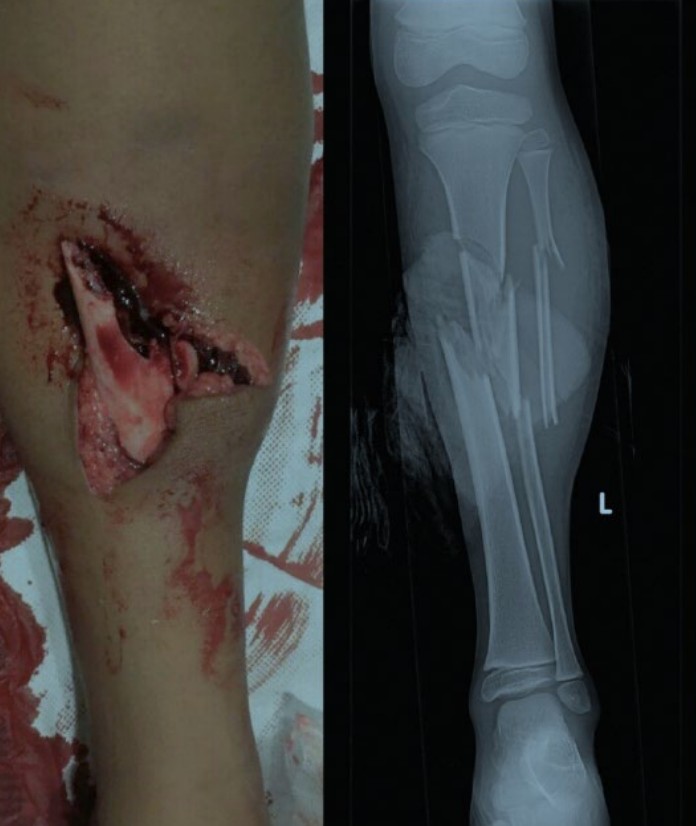

Paediatric open tibial fracture

A 7-year-old boy is thrown from a horse and sustains isolated injuries to the left lower leg. An image and …